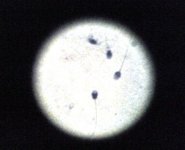

精液富含蛋白质与运动饮料相似

凤凰科技讯 北京时间9月24日消息, 国外媒体报道,一项最新研究发现,某些雌性物种会把雄性精液作为天然超...